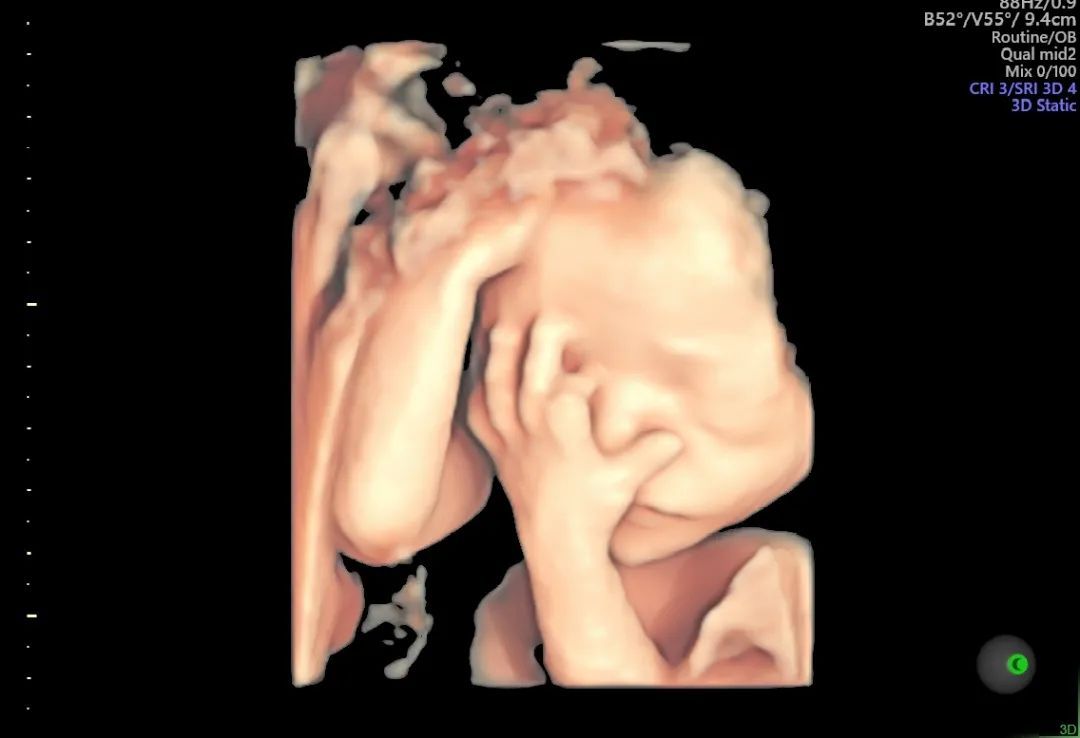

我们曾遇到过这样的情况,和平特邀超声专家邱博士在为一位准妈妈检查的过程中,发现了脐带扭转的问题。

▲邱博士所作脐带扭转四维图像

这种情况一旦没有及时发现,很可能会阻碍胎儿血液流动,引起母胎之间血氧运输及物质交换障碍。一次及时的超声检查,防患于未然,避免了可能发生的更大风险。